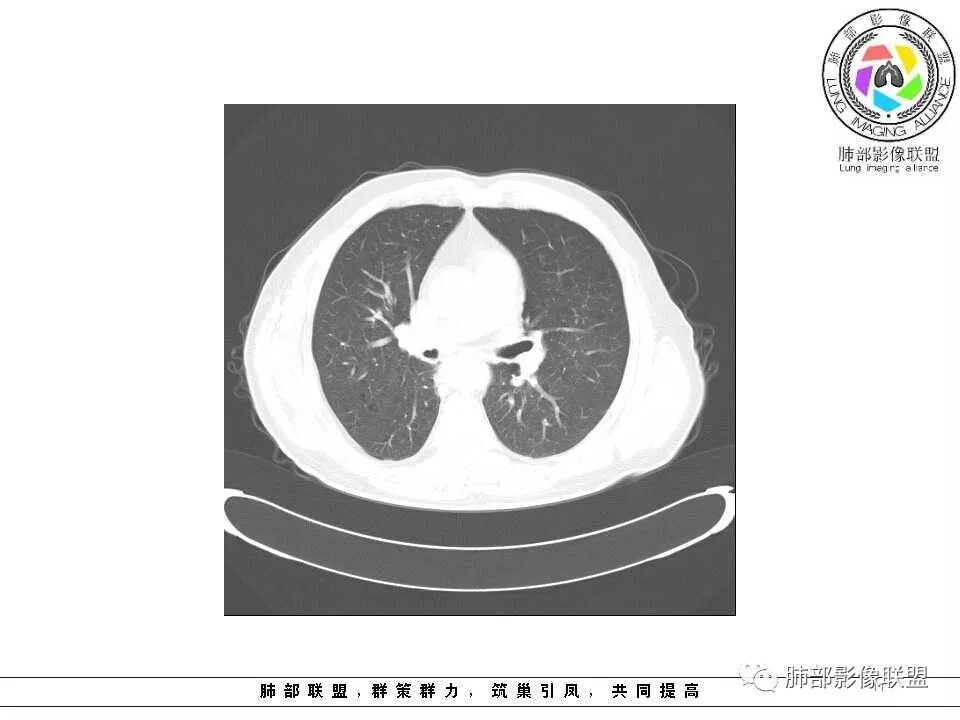

影像学特点:肺气肿背景下在大概一年的时间里出现了一个光滑的小结节,因为图像给的不是太薄,与支气管的关系判断不清,从结节周围出现斑片状炎症来判断,应该考虑结节位于支气管内,周围是阻塞性炎症,这样比较容易解释咯血

老年男性,左肺舌段见多个小结节灶及斑片状高密度灶、磨玻璃影,结节灶边界清晰,光滑,无明显分叶,密度均匀,周围病灶密度不均,一年内生长,考虑恶性肿瘤并阻塞性肺炎出血,小细胞可能大。

老年男性,肺气肿基础。约一年时间出现左肺上叶舌段支气管近端结节影,远端斑片样阴影,边缘模糊。考虑近端恶性占位,远端有阻塞性炎症。

老年男性,有咳血病史,左肺上叶舌段一年时间出现新发类圆形小结节,感觉在支气管内,部分凸出气管外,没有mpr不好说,远端肺野斑片模糊影,考虑阻塞性炎症,纵隔无明显肿大淋巴结,小细胞代排,按照发展速度,类癌低度恶性,应该发展缓慢,一年病史,代排,首先考虑鳞癌并阻塞性炎症

左肺上叶舌段支气管管壁略增厚 间隔一年 管壁增厚明显 向腔外突出形成结节 管腔闭塞 远端片状及斑片影 纵隔淋巴结增大 肺气肿背景 考虑鳞癌伴阻塞性炎症可能

老年男性,咯血1月,肺气肿背景,16年左肺上叶舌段结节,左肺门疑似淋巴结肿大,呈结节感。17年左肺上叶舌段见沿支气管走行分布结节 远端阻塞性肺炎,左肺门淋巴结肿大明显,首先考虑恶性病变,鳞癌?类癌?